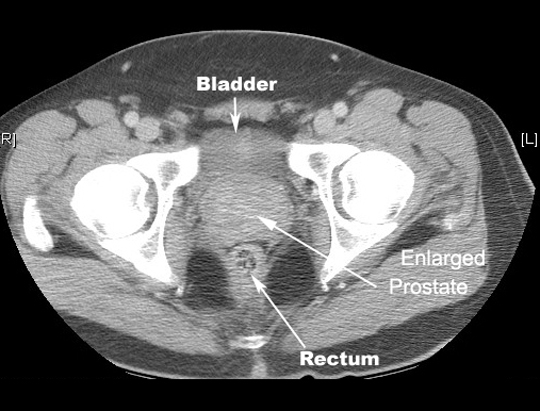

Lies around the first part of the urethra at the base of the bladder

(Tr) 4 cm x 3 cm (height) x 2 cm (AP) in size

Lies behind the symphysis pelvis

Peripheral zone and Internal zone